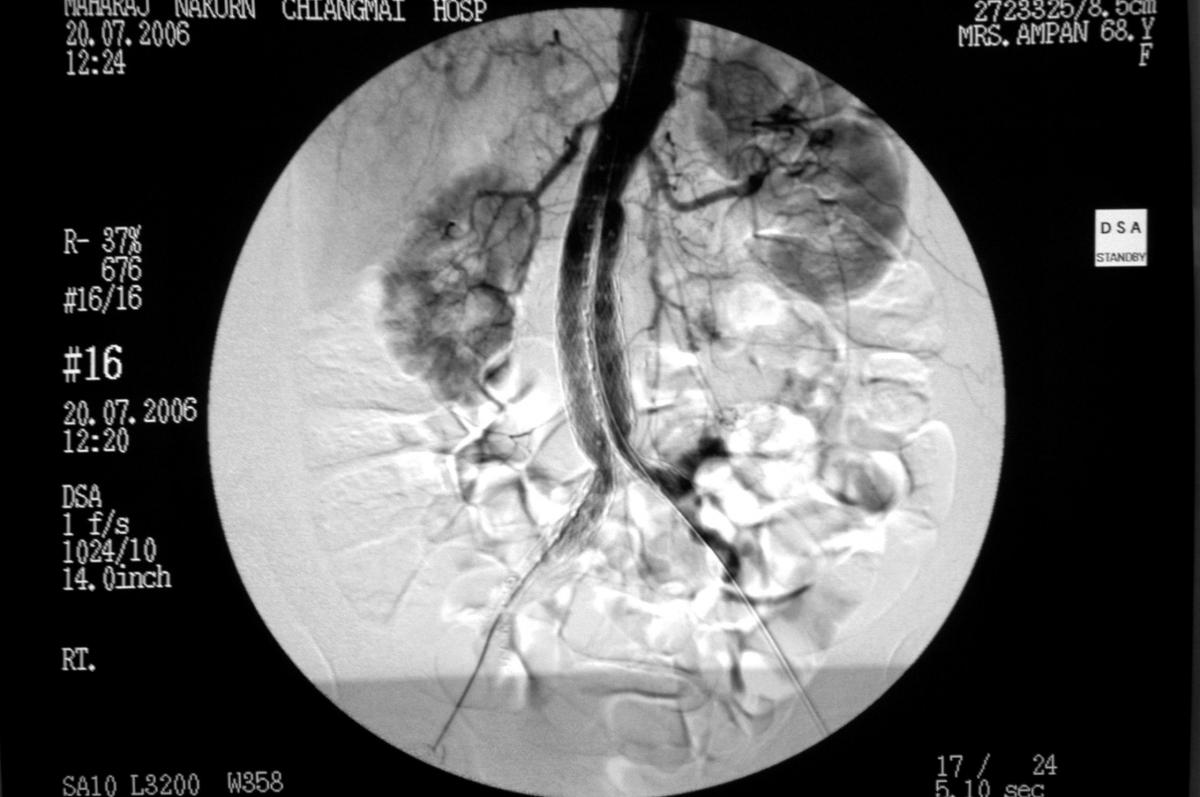

ภาพที่ 4. ประเมินตำแหน่งหลอดเลือดเทียมที่เหมาะสมจากการฉีดสารทึบแสง

และดูจากจอมอนิเตอร์

ข้อจำกัดของ EVAR และการเลือกหลอดเลือดเทียม (ภาพที่ 3, 4)

ความเหมาะสมสำหรับ EVAR ขึ้นอยู่กับลักษณะจำเพาะทางกายวิภาคศาสตร์ของหลอดเลือด13,14 ตามตารางที่ 1. จุดสำคัญที่สุดคือความยาวของหลอดเลือดปกติส่วนต้นและปลายต่อหลอดเลือดโป่งพอง ส่วนใหญ่แล้วหลอดเลือดโป่งพองจะอยู่เลยจุดแยก และลามลงไปถึงหลอดเลือดแดงไอลิแอก. ดังนั้นจึงพบว่า สำหรับ EVAR จะใช้ bifurcate device (aorto-biiliac) เป็นส่วนมาก ต่างจากการเปิดหน้าท้องผ่าตัดซ่อมหลอดเลือดโป่งพอง ซึ่งจะใช้ tube graft มากว่า เพราะสามารถเย็บต่อได้ที่ขอบผนังเอออร์ตาที่ติดกับรูเปิดของหลอดเลือดแดงคัมม่อนไอลิแอก.15